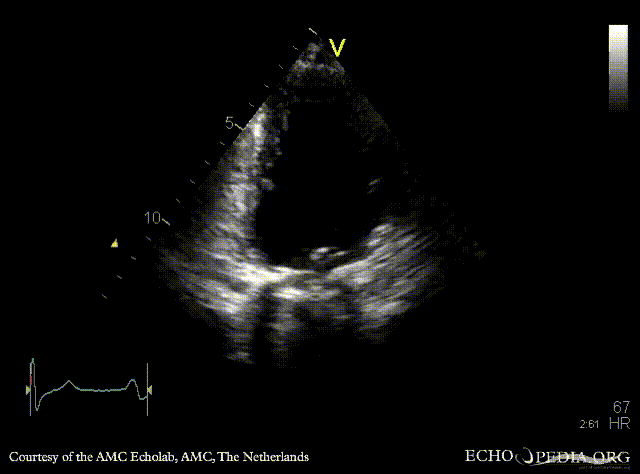

Mechanical mitral valve prosthesis

Courtesy of: AMC Echolab, AMC, The Netherlands

PLAX: mechanical mitral valve prosthesis, dilated left ventricle and left atrium PLAX with Color Dopler: no mitral regurgitation